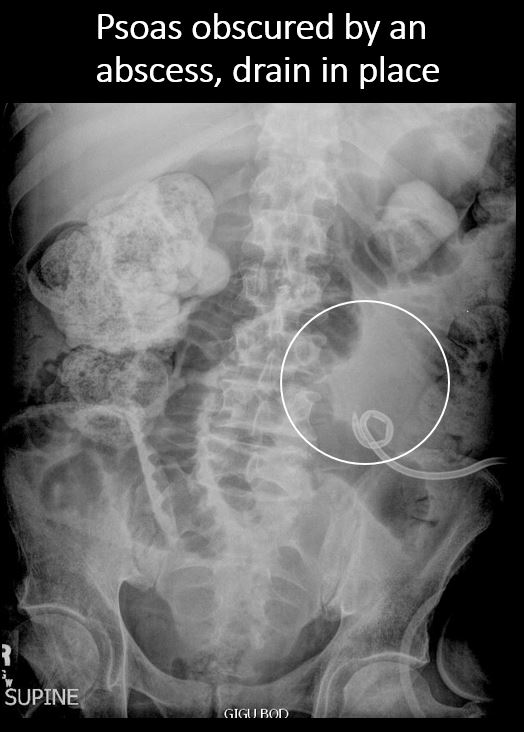

The right or left psoas muscle is obscured. |

No | NA |

There is retroperitoneal air outlining the right psoas muscle likely from duodenal perforation, from recent endoscopy. There are a few distended loops of small bowel in the mid and lower abdomen.